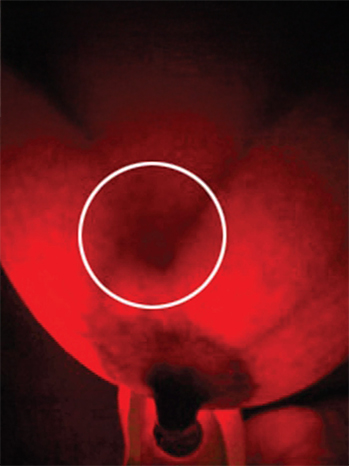

iSCANBREAST has been designed to enhance the Breast self-check rather than replace it. By feeling the breasts with your hands you can become more aware of the shape, texture and size of your breasts which will ultimately increase your breast awareness but, what you cannot do is get an internal view of any issues before they become visible to natural sight or touch. What about the areas you can’t see, feel or touch? You’d be forgiven for thinking that all is well once you have completed your self-check by hand and haven’t found anything unusual, but if there is a problem already starting to form below the surface, there is a high probability that you wouldn’t pick this up by hand checking alone.